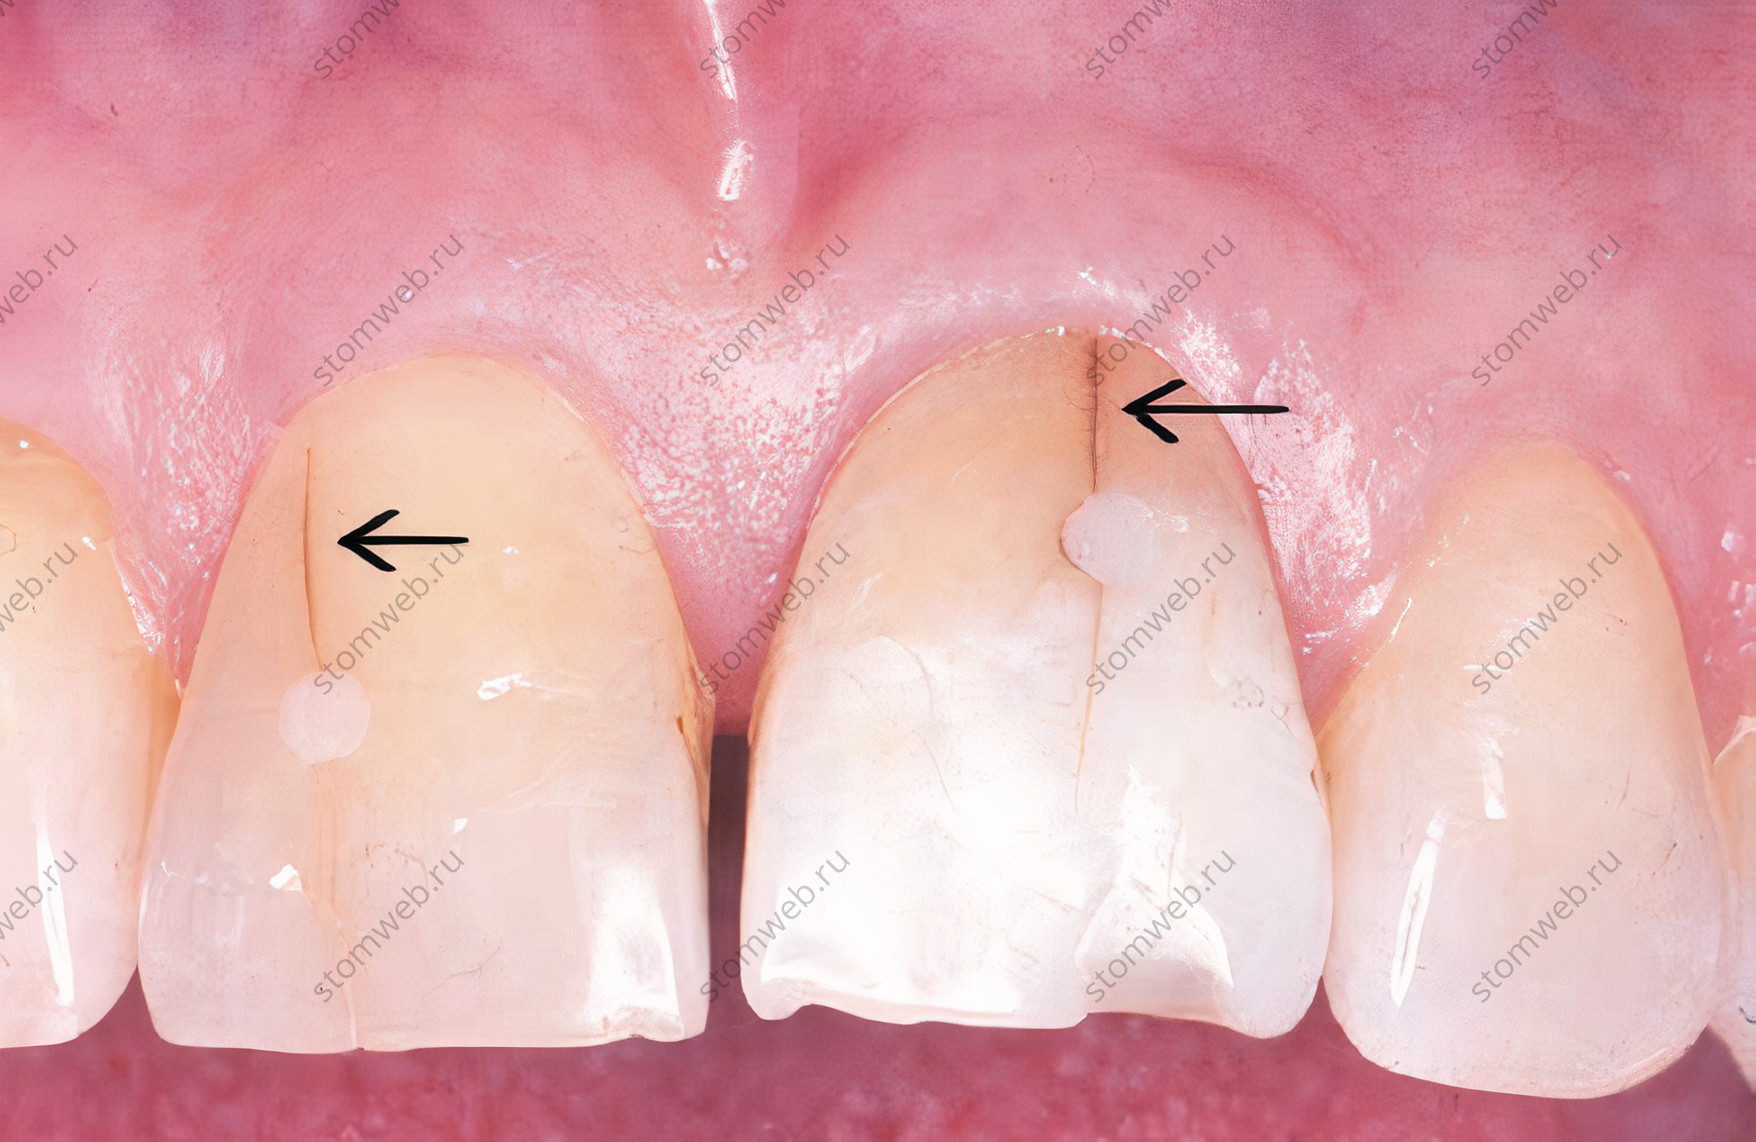

Два других термина представляют собой крайние значения переломов коронок. Линии трещин - это видимые трещины, затрагивающие только эмаль (рис. 5). Они могут распространяться на нижележащий дентин, но это обычно трудно определить. Они не связаны с симптомами, и лечение ведется по эстетическим показаниям. Другая крайность - это полный перелом зуба, который проходит через оба краевых гребня, обычно в мезио-дистальном направлении, полностью разделяя зуб на два отдельных сегмента (рис. 6). Для удобства в этой главе термин «перелом» обычно используется для различных переломов коронок.

Рисунок 5. Центральные резцы верхней челюсти с множеством трещин эмали (указано стрелками)